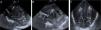

Cortes sagitales (A y B) y coronal (C) de la ecografía mostrando múltiples imágenes puntiformes y lineales hiperecogénicas, birrefringentes en la sustancia blanca profunda periventricular bilateral (flechas en A y C) y en el surco tálamo-caudado derecho (flecha en B) pudiendo ser atribuibles a embolismo cerebral.